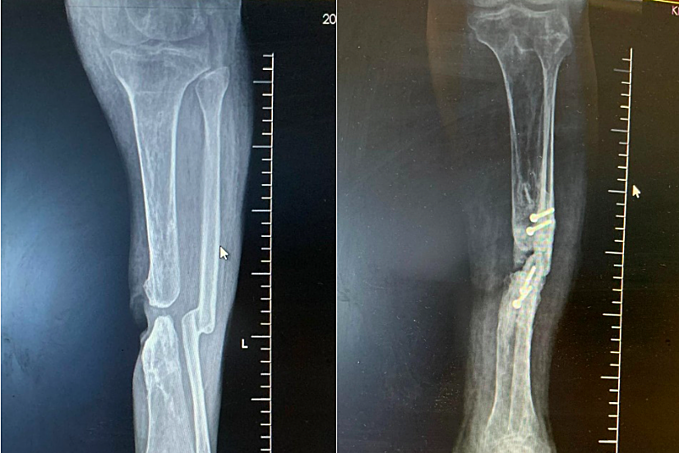

6 tháng trước, bà đến Bệnh viện Hoàn Mỹ Sài Gòn khám. Chẩn đoán hình ảnh cho thấy chân trái bị mất một đoạn xương chày khoảng 3 cm.

Sau phẫu thuật, hình ảnh X-quang ghi nhận xương ghép lấp đầy khoảng chày mác và đoạn xương chày bị mất. Chân bệnh nhân dần hồi phục và hiện xương đã lành chắc.